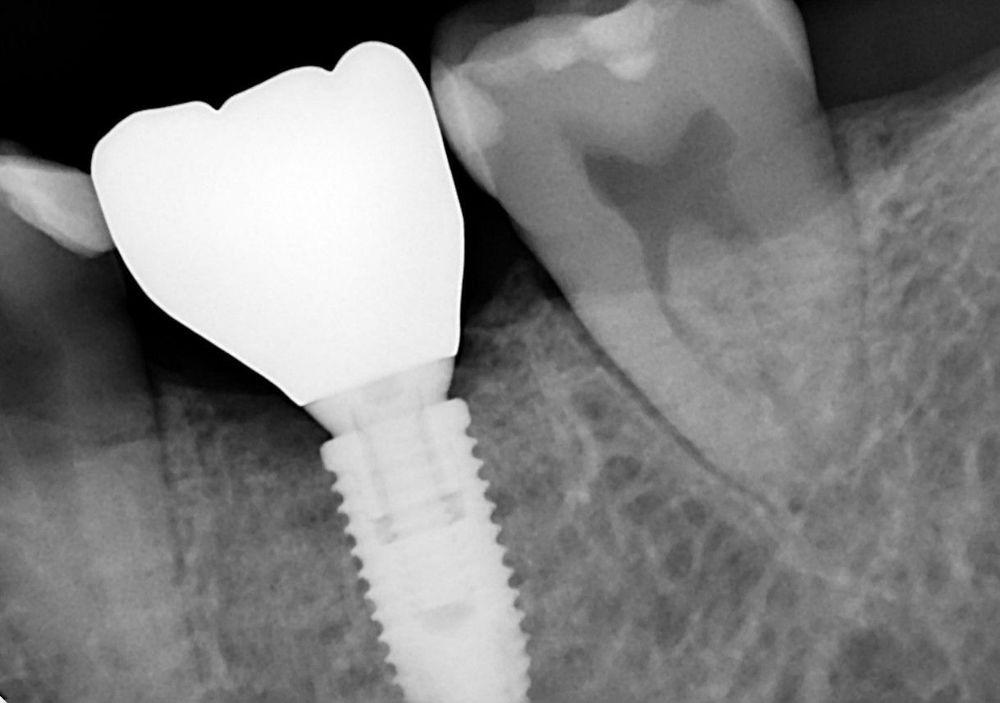

По прошествии трёх месяцев, после подтверждённой остеоинтеграции и стабилизации мягких тканей, формирователь был извлечён, и выполнено изготовление временной коронки. Ещё через месяц, при отсутствии воспаления и при полной готовности тканей, была проведена финальная реставрация: установка постоянной ортопедической конструкции на имплантат.